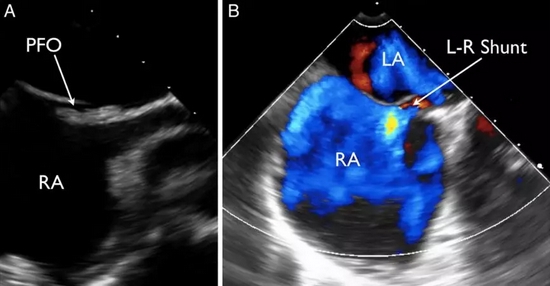

列位看官,你们肯定忽视了一种心脏疾病所致的偏头痛:卵圆孔未闭。

卵圆孔其实是心房原发隔与继发隔之间的一个缝隙。由于这个解剖结构的存在,当情绪激动等其他原因导致胸腔内压力过高时,可能会导致心房之间出现右向左的分流。因静脉血中化学物质如 5-羟色胺等血管活性物质较多,在分流后会导致脑血管扩张出现偏头痛。

所以在临床中会有一些不明原因偏头痛的患者,能够卵圆孔未闭封堵中获益。

卵圆孔未闭,一般是左向右分流,在右心压力升高时,可出现右向左分流 卵圆孔未闭,一般是左向右分流,在右心压力升高时,可出现右向左分流

除功能性头痛,卵圆孔未闭更大的潜在风险,是导致矛盾栓塞。即来自下肢深静脉或右心系统的血栓,通过卵圆孔进入左心系统,继而导致外周动脉尤其是脑血管栓塞。